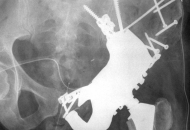

Spiron® / CoxaFit® – OP

Workshop Spiron® Vietnam